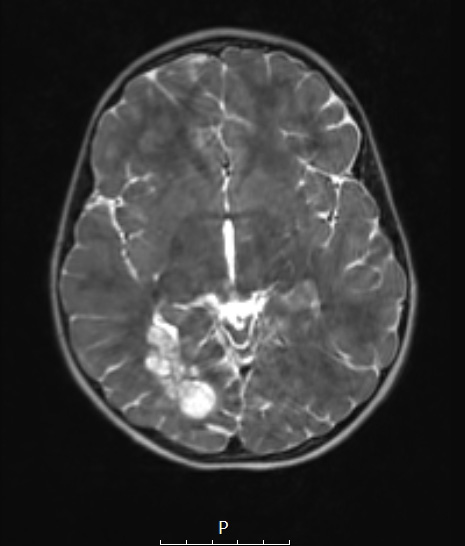

Washington University Experience | NEOPLASMS (NEURONAL) | DNET | 29A3 DNET & Heterotopia (Case 29) T2wC 3a

29A3-5 The lesion also is multinodular and hyperintense in this T2-weighted scan as seen in axial (29A3), coronal (29A4) and sagittal (29A5) sections.